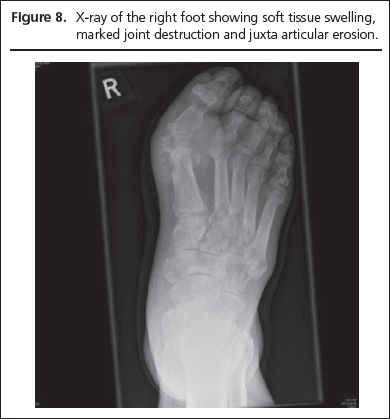

An 83 year old man with type 2 diabetes presented to the multidisciplinary foot clinic with bilateral foot ulcers. He was recovering from a ray amputation of the left first toe due to osteomyelitis of the first metatarsal head but had developed new minute ulcers on the medial aspect of the right hallux. At presentation the patient had received antibiotic therapy for nearly four months in the community. There was suspicion of underlying osteomyelitis in the right foot in the presence of non healing ulcers. The most prominent clinical finding was a red, hot and swollen right first MTP joint. A high index of suspicion led to immediate incision and drainage. A copious quantity of chalky semi-liquid material was drained (Figure 7). The diagnosis of gout was confirmed by the presence of negatively birefringent crystals under polarised light microscopy. A thorough surgical debridement was carried out with complete removal of underlying gouty tophi which had invaded the underlying bone and joint space resulting in significant bone and joint destruction (Figure 8).

Figure 7

Figure 8